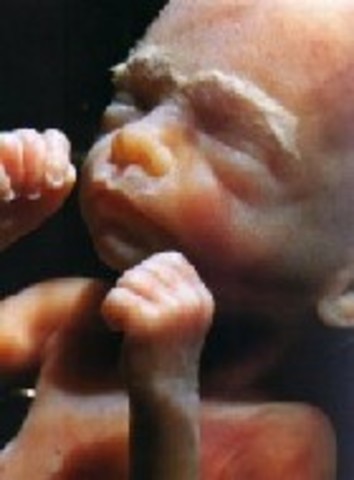

• Week 9: Phalanges

Week 9: Phalanges

The embryo is now at 30 mm. Cartilage and bones are developing, as are finger and toes starting to take their shape. Facial features such as the tongue and upper lip are being identifed with the embryo. The heart is now fully developed. The head is beginning to enlarge in size due to rapid growth of the brain.

Facts:During this week of pregnancy your baby is now swimming round in a little bag of fluid

-During this week, the baby's veins are clearly visible